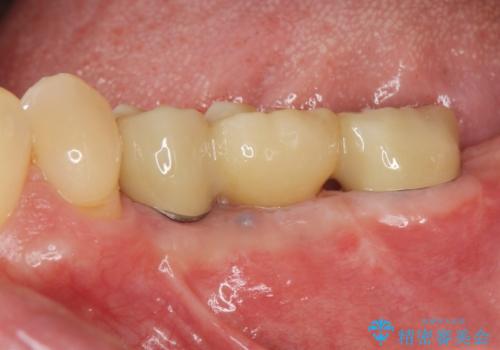

[ 2歯連続欠損 ] インプラントによる機能回復

![[ 2歯連続欠損 ] インプラントによる機能回復 の症例 治療後](https://seimitsushinbi.jp/wp/wp-content/uploads/2021/06/e9f570392fb27dc25eb48513f3cfe24e-500x350.jpg?v=1623390671)